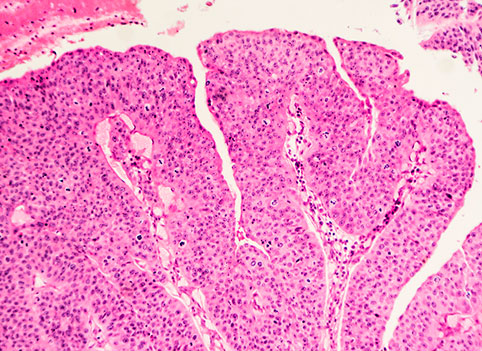

Морфологический диагноз устанавливается в соответствии с классификацией ВОЗ на основании данных биопсии, полученной с помощью трансуретральной (ТУР) резекции первичной опухоли (таблица №1).

Также в соответствии с последними критериями ВОЗ опухоли должны классифицироваться как высоко- и низкодифференцированные опухоли, но могут подразделяться и согласно классификации 1973 года на высокодифференцированные, умереннодифференцированные и низкодифференцированные опухоли мочевого пузыря. В 90% случаев диагностируется переходно-клеточный рак мочевого пузыря.

Морфологическая классификация подразумевает деление согласно гистологическому строению злокачественного образования:

- Эпителиальные (карцинома);

- Неэпителиальные (саркома).

Эпителиальные новообразования мочевого пузыря

Наиболее часто диагностируется переходно-клеточный рак. Другое название патологии уротелиальная карцинома. По степени злокачественности выделяют низкодифференцированную и высокодифференцированную карциному. Низкодифференцированная уротелиома является более опасной формой, хуже поддается лечению и чаще возвращается.